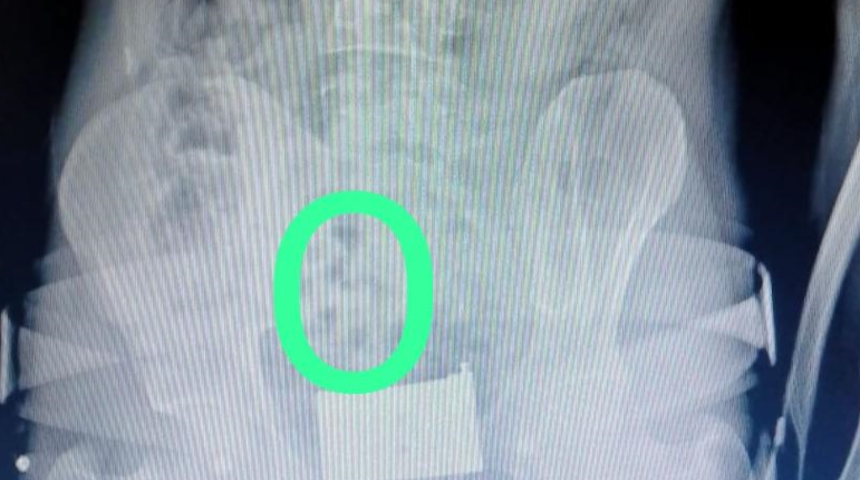

Muayene ve röntgeni çekilen İran uyruklu A.F. ve S.G'nin 558,83 gram eroni 64 kapsül haline getirerek yuttukları tespit edildi. Gözaltına alınan zanlılar, emniyetteki işlemlerinin ardından sevk edildikleri adliyede çıkarıldıkları sulh ceza hakimliğince tutuklandı.